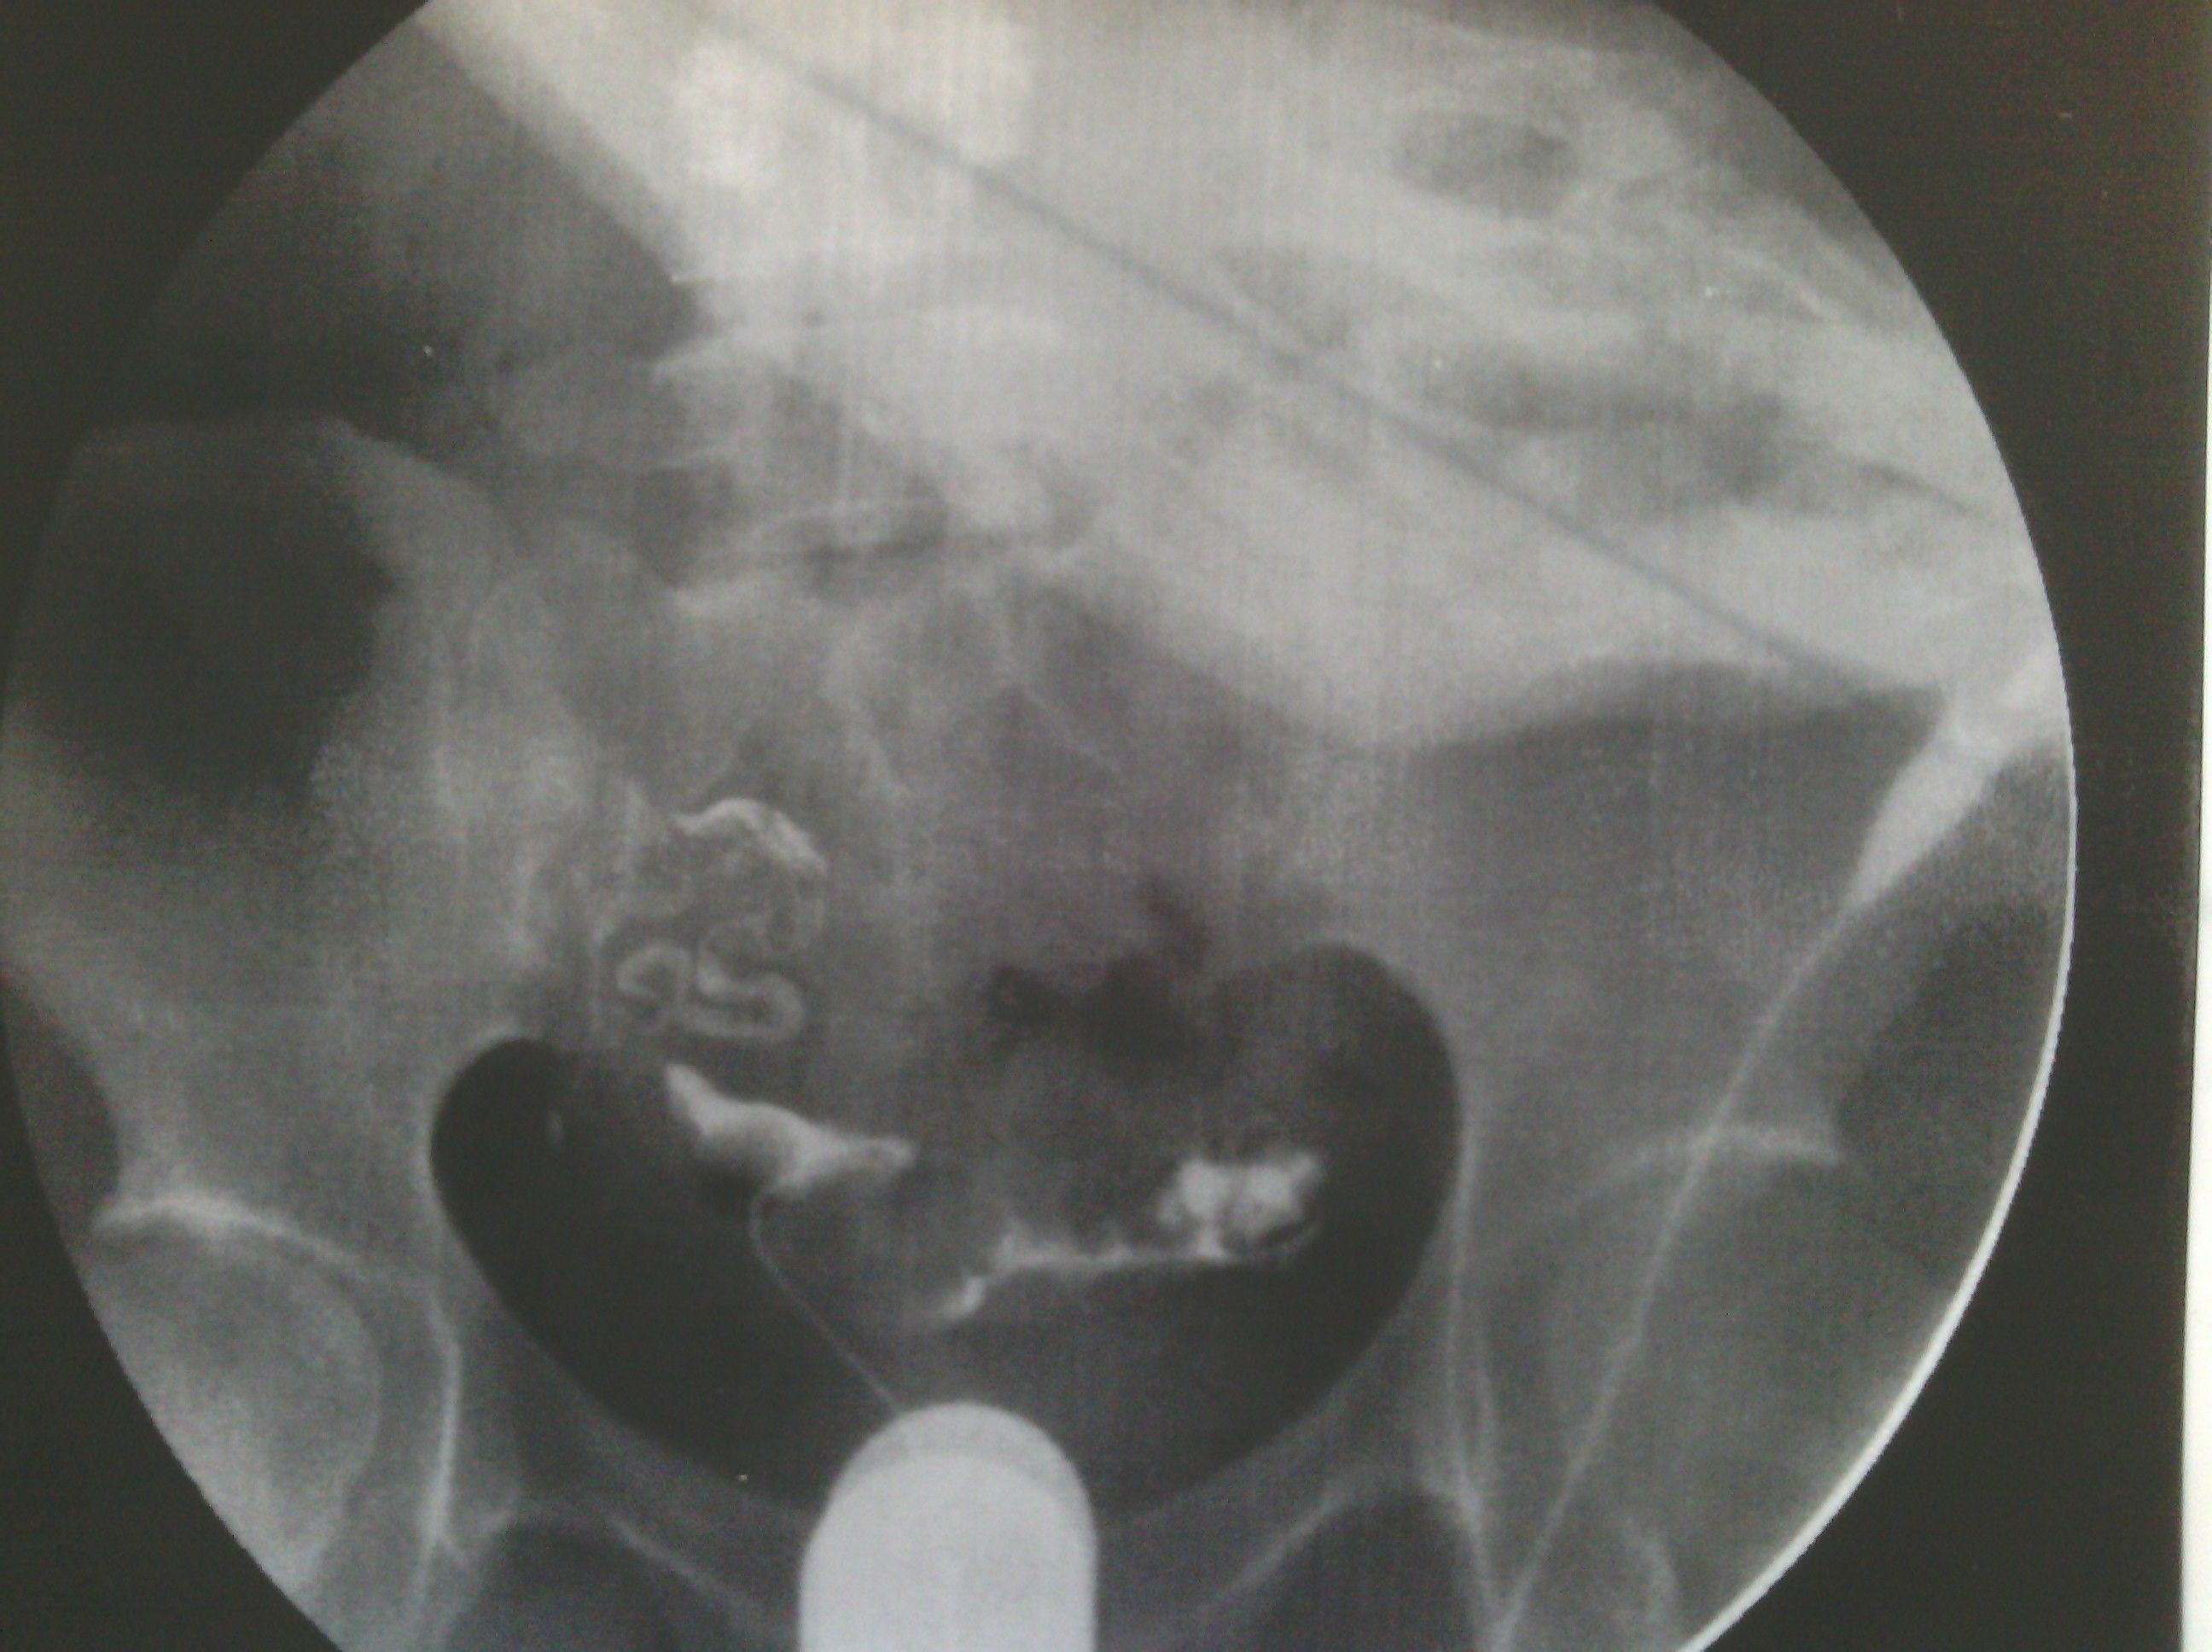

最新输卵管造影图片,麻烦各位大侠帮忙看看,纠结中 各位好,这是我11月6日做的输卵管造影图片,麻烦给看看现在是什么情况。在医院光说通而不畅有粘连,也没说哪个部位粘连,具体的是哪个部位有毛病呢?是间质部,峡部或是壶部。说少量弥散,然而弥散的片子也没延迟拍摄,是造影后直接就出来了,那判断的标准准确吗?看了好几年的病了,慕名到哪个医院去了,都没给过我合理化的建议,都是到哪家,哪家哪个拿手就推荐你做哪个,我现在看见医院两个字就想吐。我就是想,死,我也得死个明白。麻烦各位好心人看看我的片子给我一个合理化建议。现在的输卵管造影是个什么情况应该怎样治疗,在此拜谢各位了。我没啥财富值,对不起各位了。望能看片子解释一二,不胜感激。 点击展开 母婴用户710320885 2013-11-09 08:05 为您推荐: 其他回答 片子没标左右 所以我不清楚是哪边。 可以告诉你的是 面对我左边的输卵管走形上举,有黏连。面对右边的输卵管扭曲扩张。整个状况不是很乐观,具体治疗请咨询妇产科医生。 匿名用户 2013-11-11 14:28 相关问题 求讲解输卵管造影图片 妇科医生专家好:请帮忙看看这份“子宫输卵管造影检查报告”: 帮忙看看造影的报告,双侧输卵管炎不能怀孕了吗?

各位好,这是我11月6日做的输卵管造影图片,麻烦给看看现在是什么情况。在医院光说通而不畅有粘连,也没说哪个部位粘连,具体的是哪个部位有毛病呢?是间质部,峡部或是壶部。说少量弥散,然而弥散的片子也没延迟拍摄,是造影后直接就出来了,那判断的标准准确吗?看了好几年的病了,慕名到哪个医院去了,都没给过我合理化的建议,都是到哪家,哪家哪个拿手就推荐你做哪个,我现在看见医院两个字就想吐。我就是想,死,我也得死个明白。麻烦各位好心人看看我的片子给我一个合理化建议。现在的输卵管造影是个什么情况应该怎样治疗,在此拜谢各位了。我没啥财富值,对不起各位了。望能看片子解释一二,不胜感激。